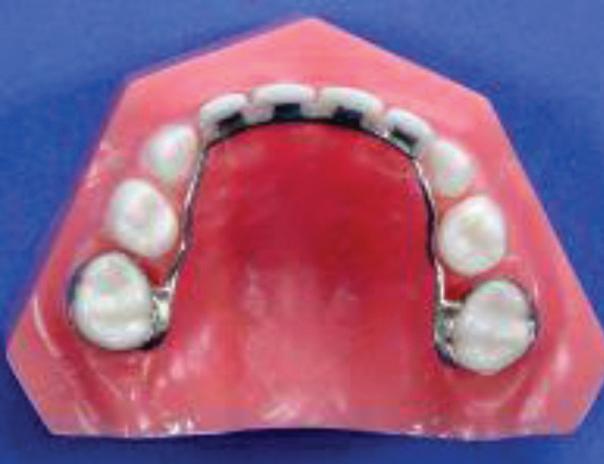

Pediatric Partial Denture to Replace Missing Teeth

Strengthening Smiles

Understanding the Importance Of Splinting Periodontally Involved Teeth

By Marc P. Stanard, DDS, PC

Periodontal disease affects millions worldwide, jeopardizing not just the health of teeth but the overall well-being of individuals. Among the treatment modalities available, splinting of periodontally involved teeth emerges as a significant strategy in preserving dental health and function. Splinting involves bonding multiple teeth together to provide stability and support, thereby preventing further damage and facilitating healing.

Understanding the role and benefits of splinting is crucial for both patients and dental professionals in combating periodontal disease effectively.

Periodontal disease, characterized by inflammation and infection of the gums and surrounding tissues, often leads to tooth mobility— a distressing symptom indicating significant tissue and bone loss. Tooth mobility not only affects chewing and speaking but also poses a threat of tooth loss if left untreated. Splinting offers a solution by redistributing forces among the connected teeth, reducing individual tooth stress and enhancing overall stability.

The process of splinting begins with a comprehensive assessment of the patient’s periodontal condition. Once the severity of mobility and bone loss is determined, suitable splinting techniques are chosen. Common methods include using

wires, resin materials, or a combination of both to connect the affected teeth. These splints can be temporary or permanent, depending on the patient’s needs and the clinician’s recommendation.

One of the primary benefits of splinting is its ability to preserve natural dentition. By stabilizing mobile teeth, splints prevent further movement, allowing the periodontal tissues to heal. This not only improves the functionality of the teeth but also enhances the patient’s quality of life, restoring confidence in their smile.

Moreover, splinting aids in maintaining proper occlusion—the alignment of teeth when the jaw is closed. By preventing excessive movement of periodontally involved teeth, splints help preserve occlusal stability, preventing complications such as TMJ disorders and premature wear of teeth.

For patients undergoing peri-

odontal treatment, understanding the importance of splinting is essential. While it may seem daunting at first, splinting offers a promising solution for stabilizing compromised teeth and preventing further deterioration. However, proper oral hygiene practices, including regular brushing, flossing, and professional cleanings, remain integral in maintaining the longevity of splinted teeth.

Splinting of periodontally involved teeth serves as a valuable tool in the management of periodontal disease. By providing stability, preserving dentition, and maintaining occlusal harmony, splints contribute significantly to improving oral health and restoring smiles. Consulting with a knowledgeable dental professional can help individuals make informed decisions regarding their periodontal treatment, ensuring a brighter, healthier future for their teeth and gums.